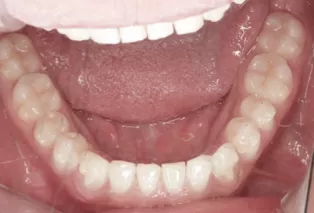

Photos intra-orales